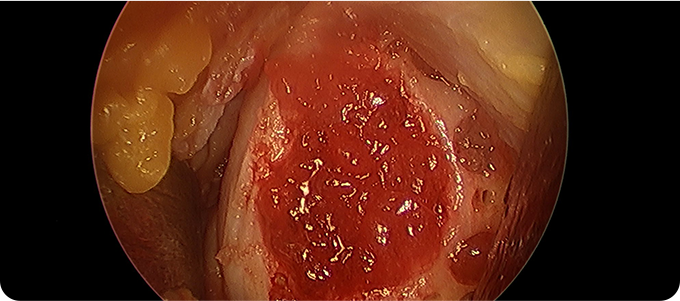

4. 수술 후 재생된 연골

수술 후 일정 기간 목발 보행, 관절 운동 제한, 물리치료 등을 통해 줄기세포가 연골로 자리잡도록 관리합니다.